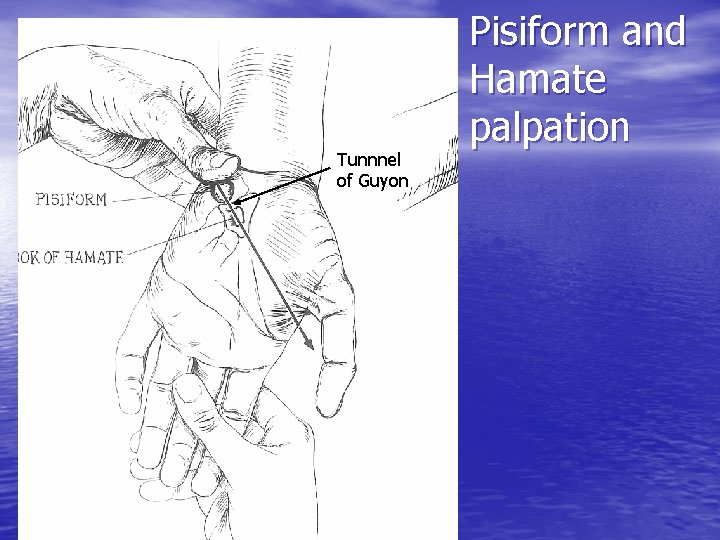

Tunnnel of Guyon Pisiform and Hamate palpation

Tunnel of Guyon • Depression between • • pisiform and hook of hamate Contains ulnar nerve and artery Site of compression injuries – unusually tender if pathology is present